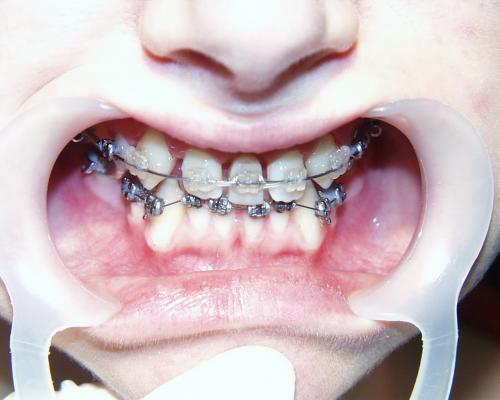

Während der Behandlung

Gleich nach Entfernung der zerstörten mittleren Schneidezähne wurde die feste Zahnspange eingesetzt. Im Bereich der Lücken wurden mit Brackets beklebte Prothesenzähne angebracht. Mit fortschreitender Verkleinerung der Lücke wurde nur noch ein Prothesenzahn belassen (mittleres Bild), der schließlich auch entfernt werden konnte. Die seitlichen Schneidezähne wurden so auf Lücke gestellt, daß sie nach Verbreiterung die Größe von mittleren Schneidezähnen annehmen konnten. Die Eckzähne wurden an Stelle der seitlichen Schneidezähne bewegt (rechtes Bild).